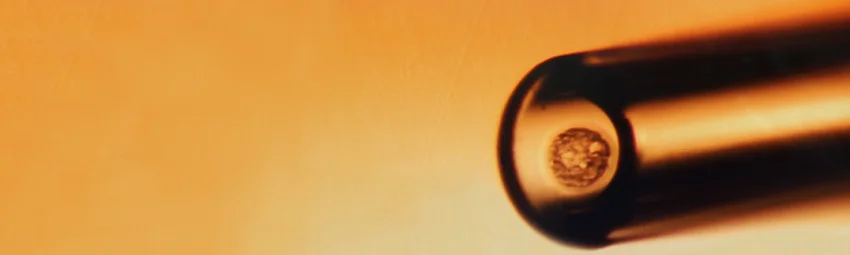

Криоконсервация — это метод мгновенного охлаждения эмбриона в специальном криопротекторном составе. Состав криопротектора (защитного раствора) и методика позволяют провести моментальное замораживание биологического материала без потери его жизнеспособности. В связи с тем, что сперматозоиды, яйцеклетки и эмбрионы чувствительны к криоконсервации, важно, чтобы на фоне охлаждения не сформировались кристаллы льда, которые могут нарушить структуру клеток. Сейчас применяется витрификация — это способ быстрой заморозки биологического материала, без риска кристаллизации. Благодаря этому методу эмбрионы можно успешно хранить десятилетиями. В нужный момент они могут быть использованы для достижения беременности.

Как происходит криозаморозка? Культивированные после пункции эмбрионы соединяют с криопротектором, после чего охлаждают методом витрификации до -196 градусов. Эмбрионы на стадии дробления и бластоцисты после оттаивания можно подсадить в матку в этот же день. Если эмбрион замораживался на стадии пронуклеусов, его культивируют и переносят в матку на этапе 2-4 клеточного эмбриона.